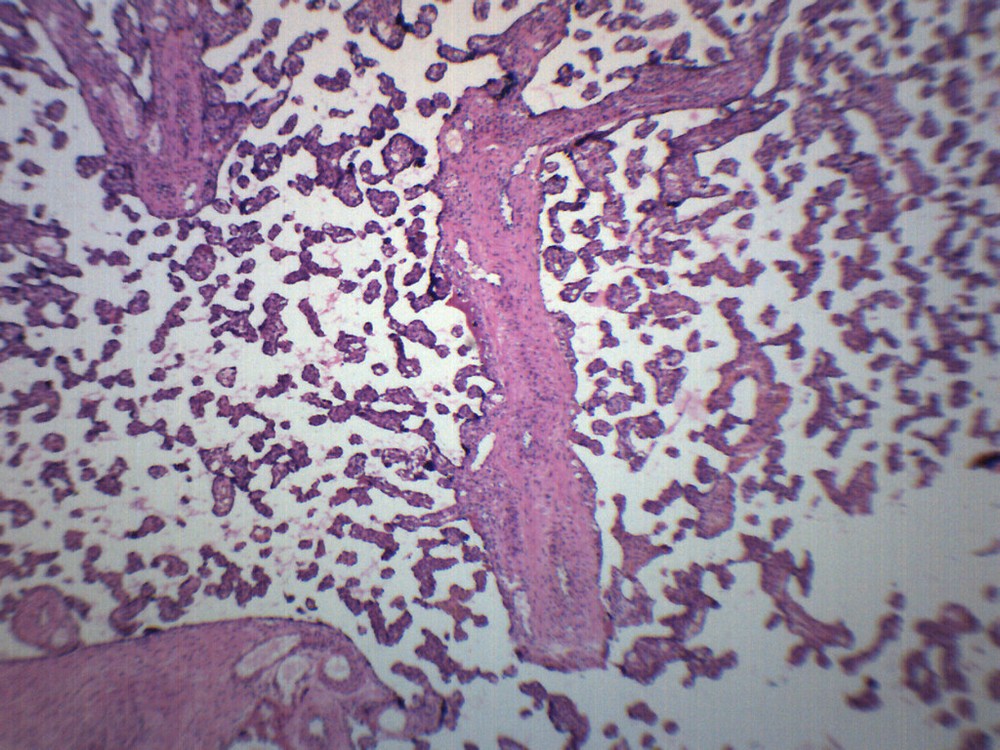

Check the listing for details. Mcmaster Method Microscope Slide - FEC (Fecal Egg Count) or Worm Count, Double C. Color: Blue, Condition: New. Listed at 32.00 USD. FECRT (Fecal Egg Count Reduction Test) Reference Guide Included. Fecal Egg Count Reduction Test (FECRT) Reference Guide Included. Designed for a quick, easy, accurate fecal egg counting process. Make evidenced based deworming protocols by doing your a Fecal Egg Count Reduction Test using the standard, original Mcmaster Egg count slide.